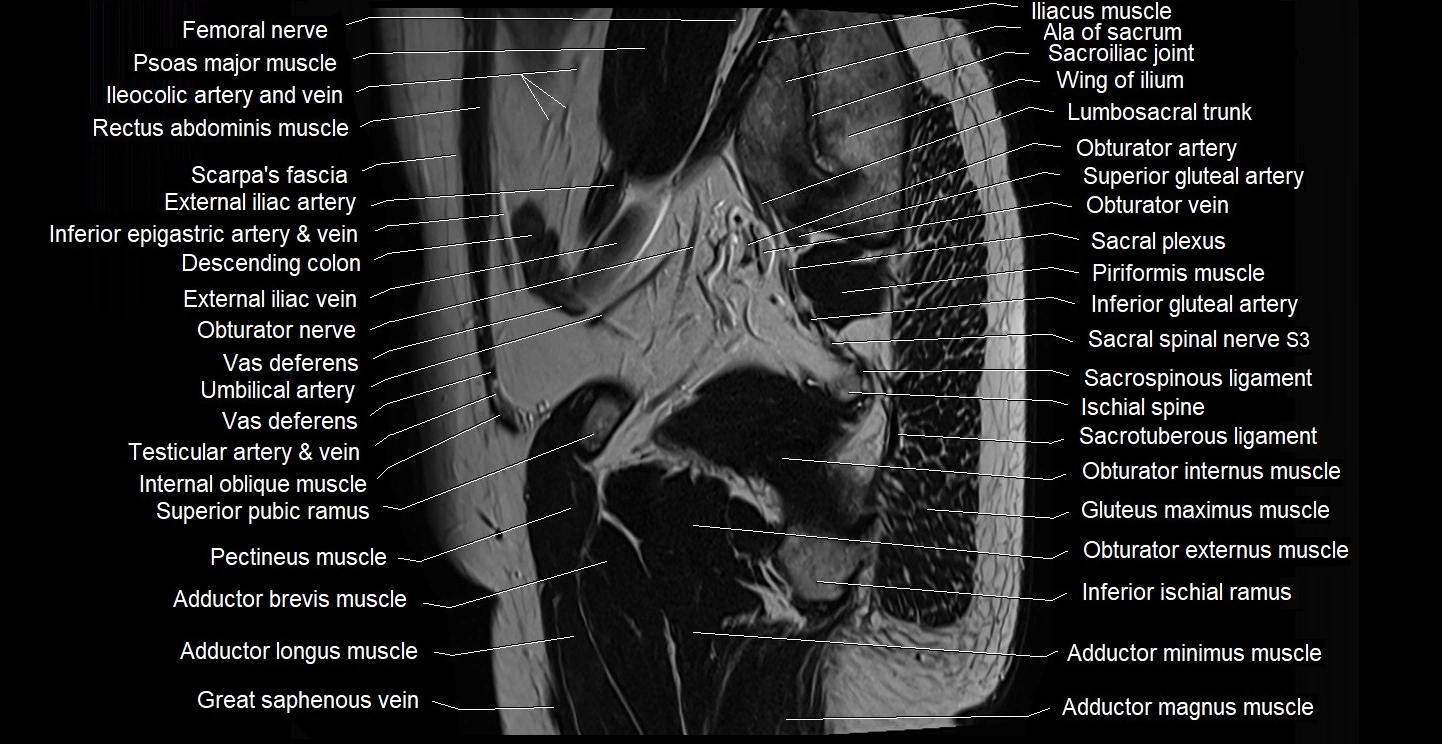

- Adductor brevis muscle

- Adductor longus muscle

- Adductor magnus muscle

- Adductor minimus muscle

- Femoral nerve

- Ileocolic artery

- Internal oblique muscle

- Lumbosacral trunk

- Obturator externus muscle

- Pectineus muscle

- Piriformis muscle

- Psoas major muscle

- Sacral plexus

- Sacroiliac joint

- Sacrospinous ligament

- Sacrotuberous ligament

- Superficial inguinal lymph nodes

- Superior gluteal artery

- Superior pubic ramus